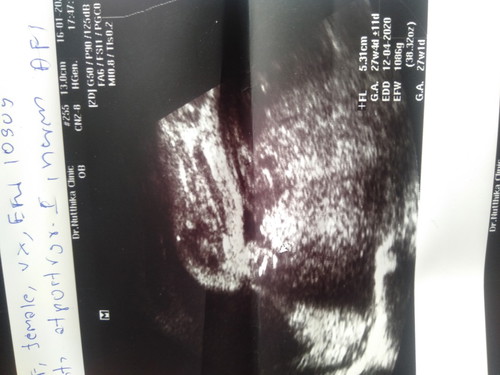

ท้องแรกค่ะ

อยากถามแม่ๆ ค่ะว่าในใบซาวด์นี้มีบอกเพศลูกไหมค่ะ ถ้ามี ญ / ช ค่ะ

Female เพศหญิง